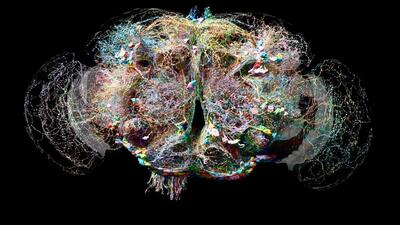

پرورش سلولهای مغزی در فضا راهکاری برای درمان بیماریهای عصبی

پرورش سلولهای مغز در محیط ریزگرانش فضا فواید خاصی دارد.

کشف شگفتانگیز؛ حافظه فقط مختص سلولهای مغز نیست

سلولهای کلیه شبیه به بافتهای عصبی نورونها یادگیری دارند.